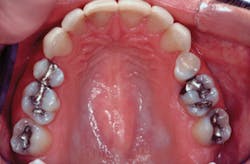

Evidence of the viability of my technique during this time can be seen with my American Academy of Cosmetic Dentistry accreditation case done in 1996. Direct posterior composite restorations on teeth Nos. 2, 3, and 15 complement the indirect restorations completed to replace faulty anterior veneers (Figs. 1 and 2).